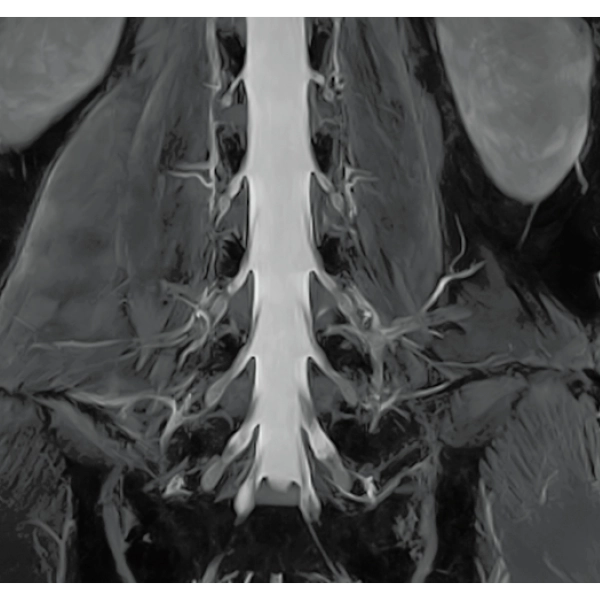

IP-RAPID x DLR Plus gives you the flexibility to shorten respiratory gated series or even replace them with breath-holds, depending on the patient’s situation. This gives you more options and a wider range of examinations to choose from.

IP-RAPID x DLR Plus can be used for basic imaging such as VolumeScan, RadialScan, HalfScan, and many other imaging methods such as MultiContrastScan FatSep and DWI.

It can also be used with time-consuming scans such as Whole Body DWI and Whole Spine imaging, providing more detailed information in many areas than previously possible.